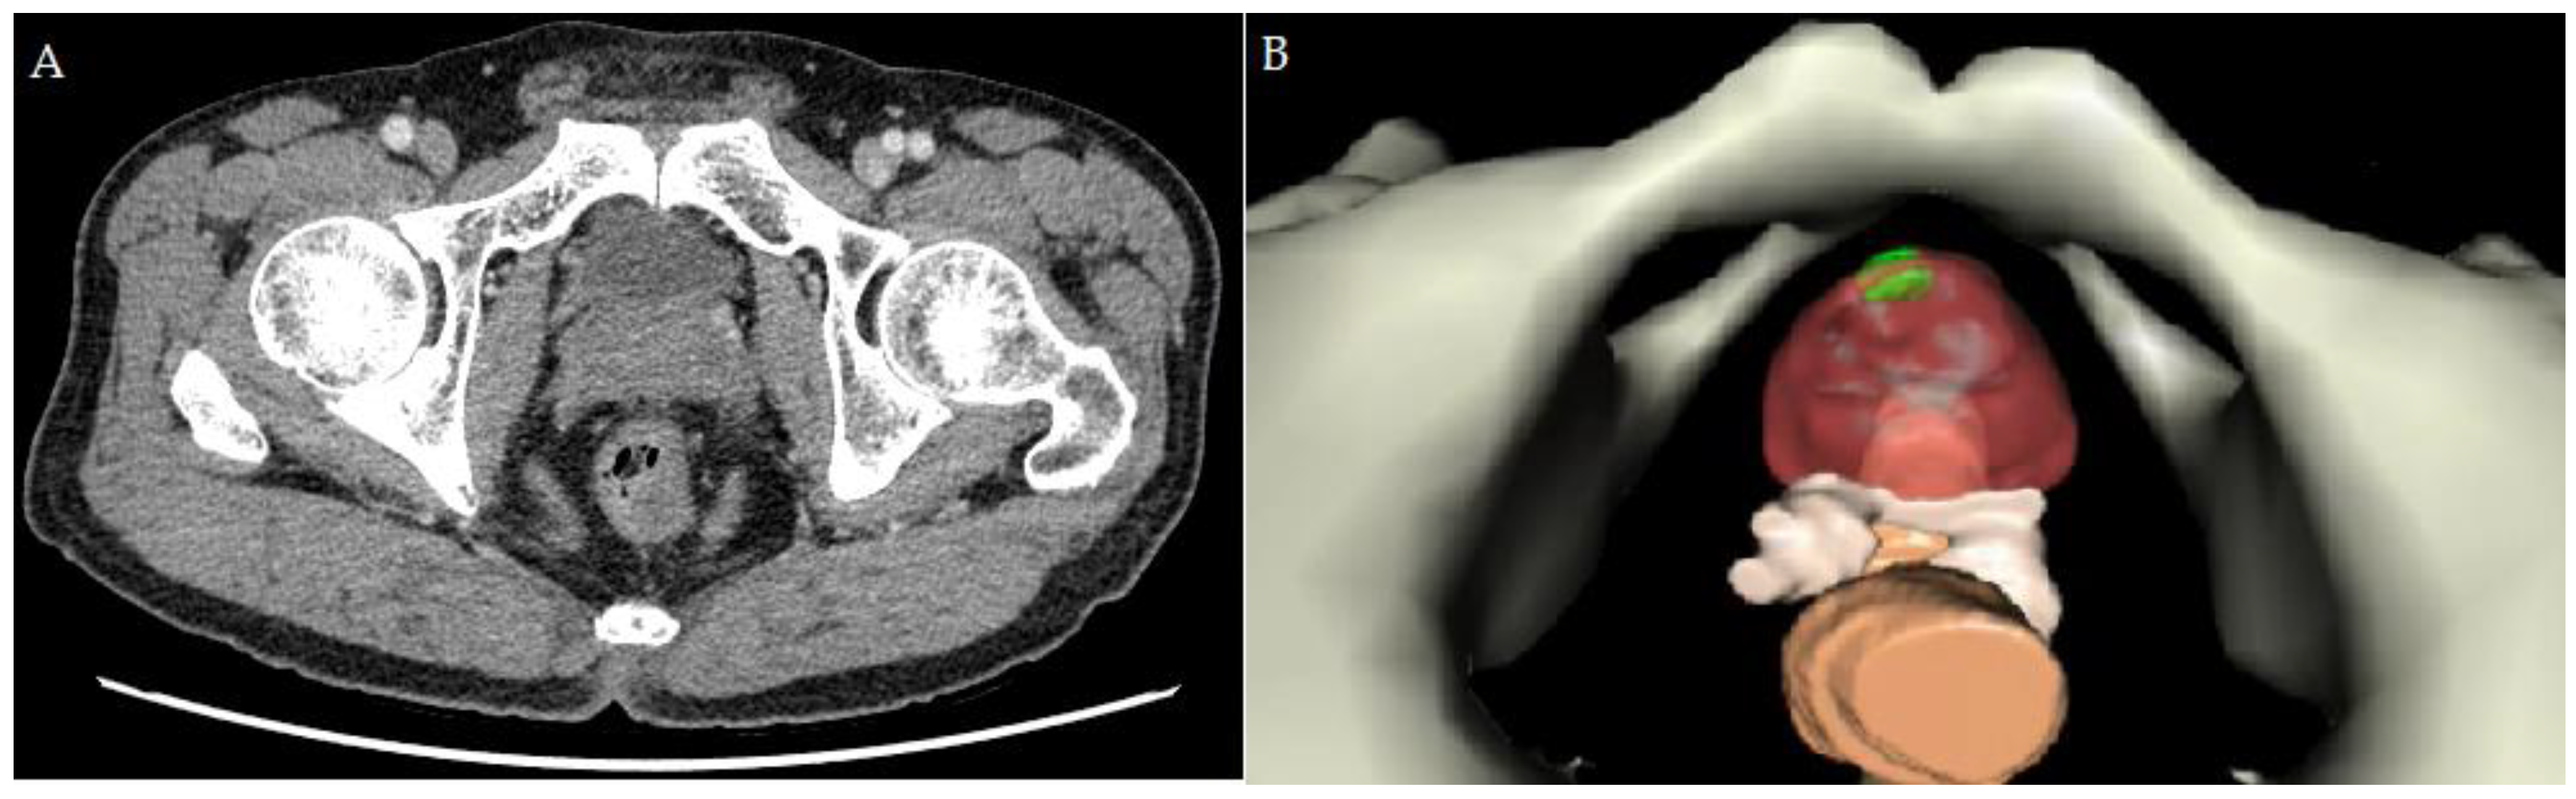

2.2. Creating the Personal 3D Model before RAPP